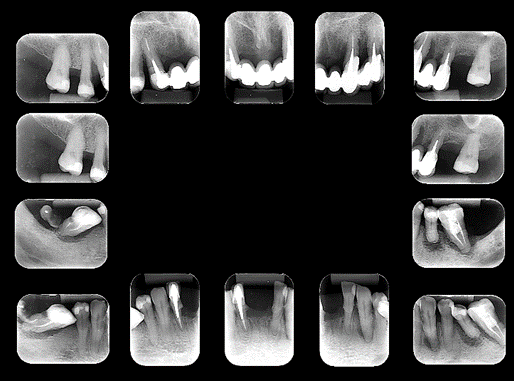

Paciente procurou tratamento protético reabilitador com queixa de dentes abalados e com mobilidade, mau hálito e sangramento gengival. Após exame clínico, radiográfico e tomográfico constatou-se a necessidade de exodontia de todos os dentes remanescente e instalação de implantes na maxila e mandíbula para posterior confecção de duas próteses do tipo Protocolo de Brånemark – prótese total fixa implantossuportada sobre implantes Maestro CM da Implacil De Bortoli, pilares do tipo mini-cônicos, barra metálica e prótese de resina acrílica, cuja abordagem encontra-se no dia a dia dos consultórios dentários.

O objetivo desse caso clínico foi de descrever uma sequência clínica de atendimento para a solução da queixa desse paciente, conforme imagens a seguir.